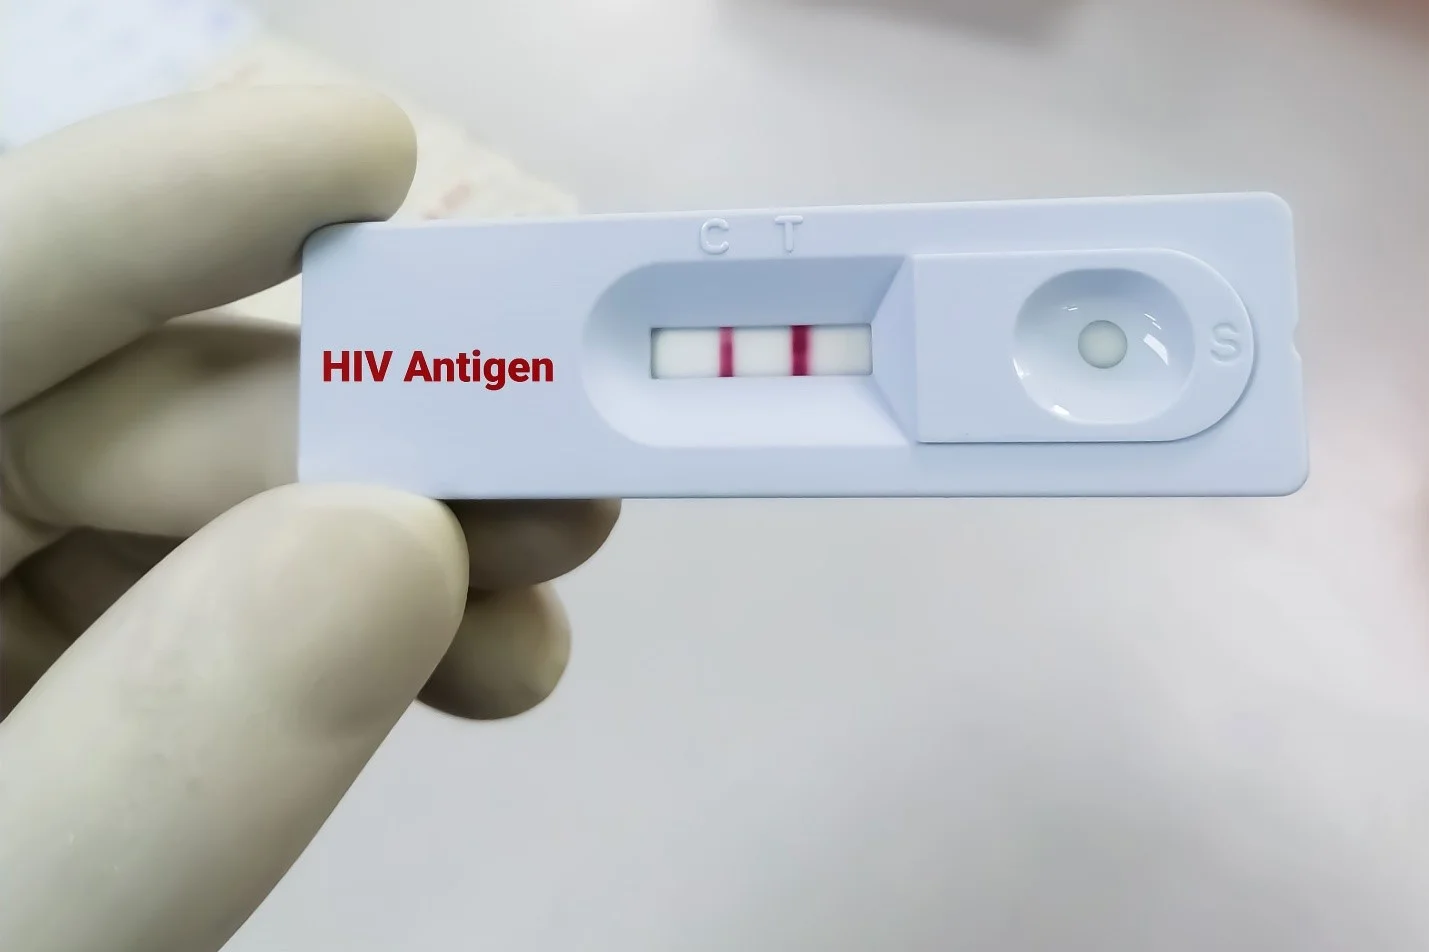

- آزمایش اچ آی وی (HIV test): در صورت داشتن علائم غیر طبیعی که ممکن است مربوط به عفونت HIV باشد، این آزمایش ممکن است انجام شود.

خطر لنفوم هوچکین در افراد آلوده به HIV – ویروسی که باعث ایدز میشود – افزایش مییابد.

عفونت با HIV – ویروسی که باعث ایدز میشود – خطر را افزایش میدهد، بنابراین یکی از راههای محدود کردن خطر، اجتناب از عوامل خطرزا شناختهشده برای HIV است، مانند مصرف مواد مخدر داخل وریدی (IV) یا رابطه جنسی محافظت نشده با بسیاری از شرکا.